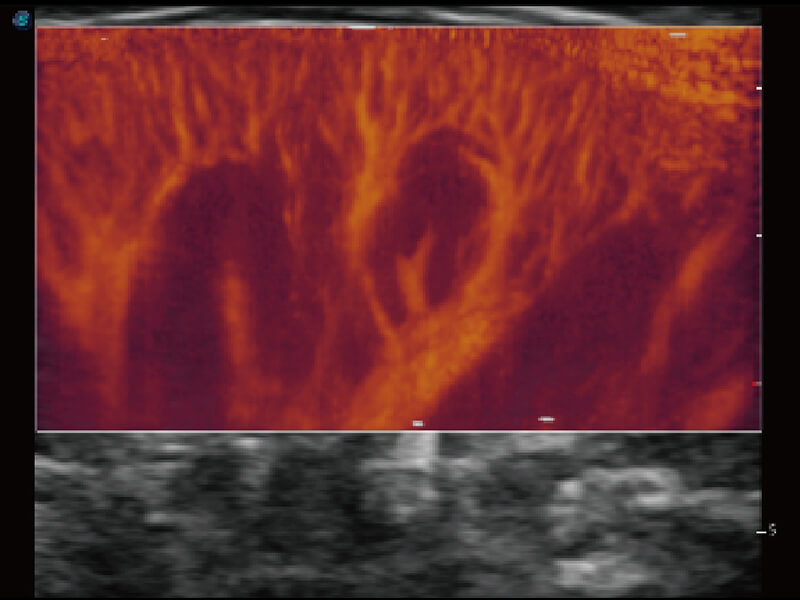

彩色多普勒超声诊断系统

成像功能

性能优异的硬件架构,极大提升超声系统的运行效率和数据处理能力。相比以往超声成像系统,Wis+平台为您带来极快的响应速度和成像帧频,提升检查流畅度。

S60探头工艺,从前端信号处理每一个环节采集无损声学数据,真实还原组织原貌,再现解剖细节。

超宽频带技术,为容积成像带来优质的二维图像基础,为您呈现丰富的结构细节,栩栩如生地展示宝宝的宫内形态以及各种组织的立体结构。